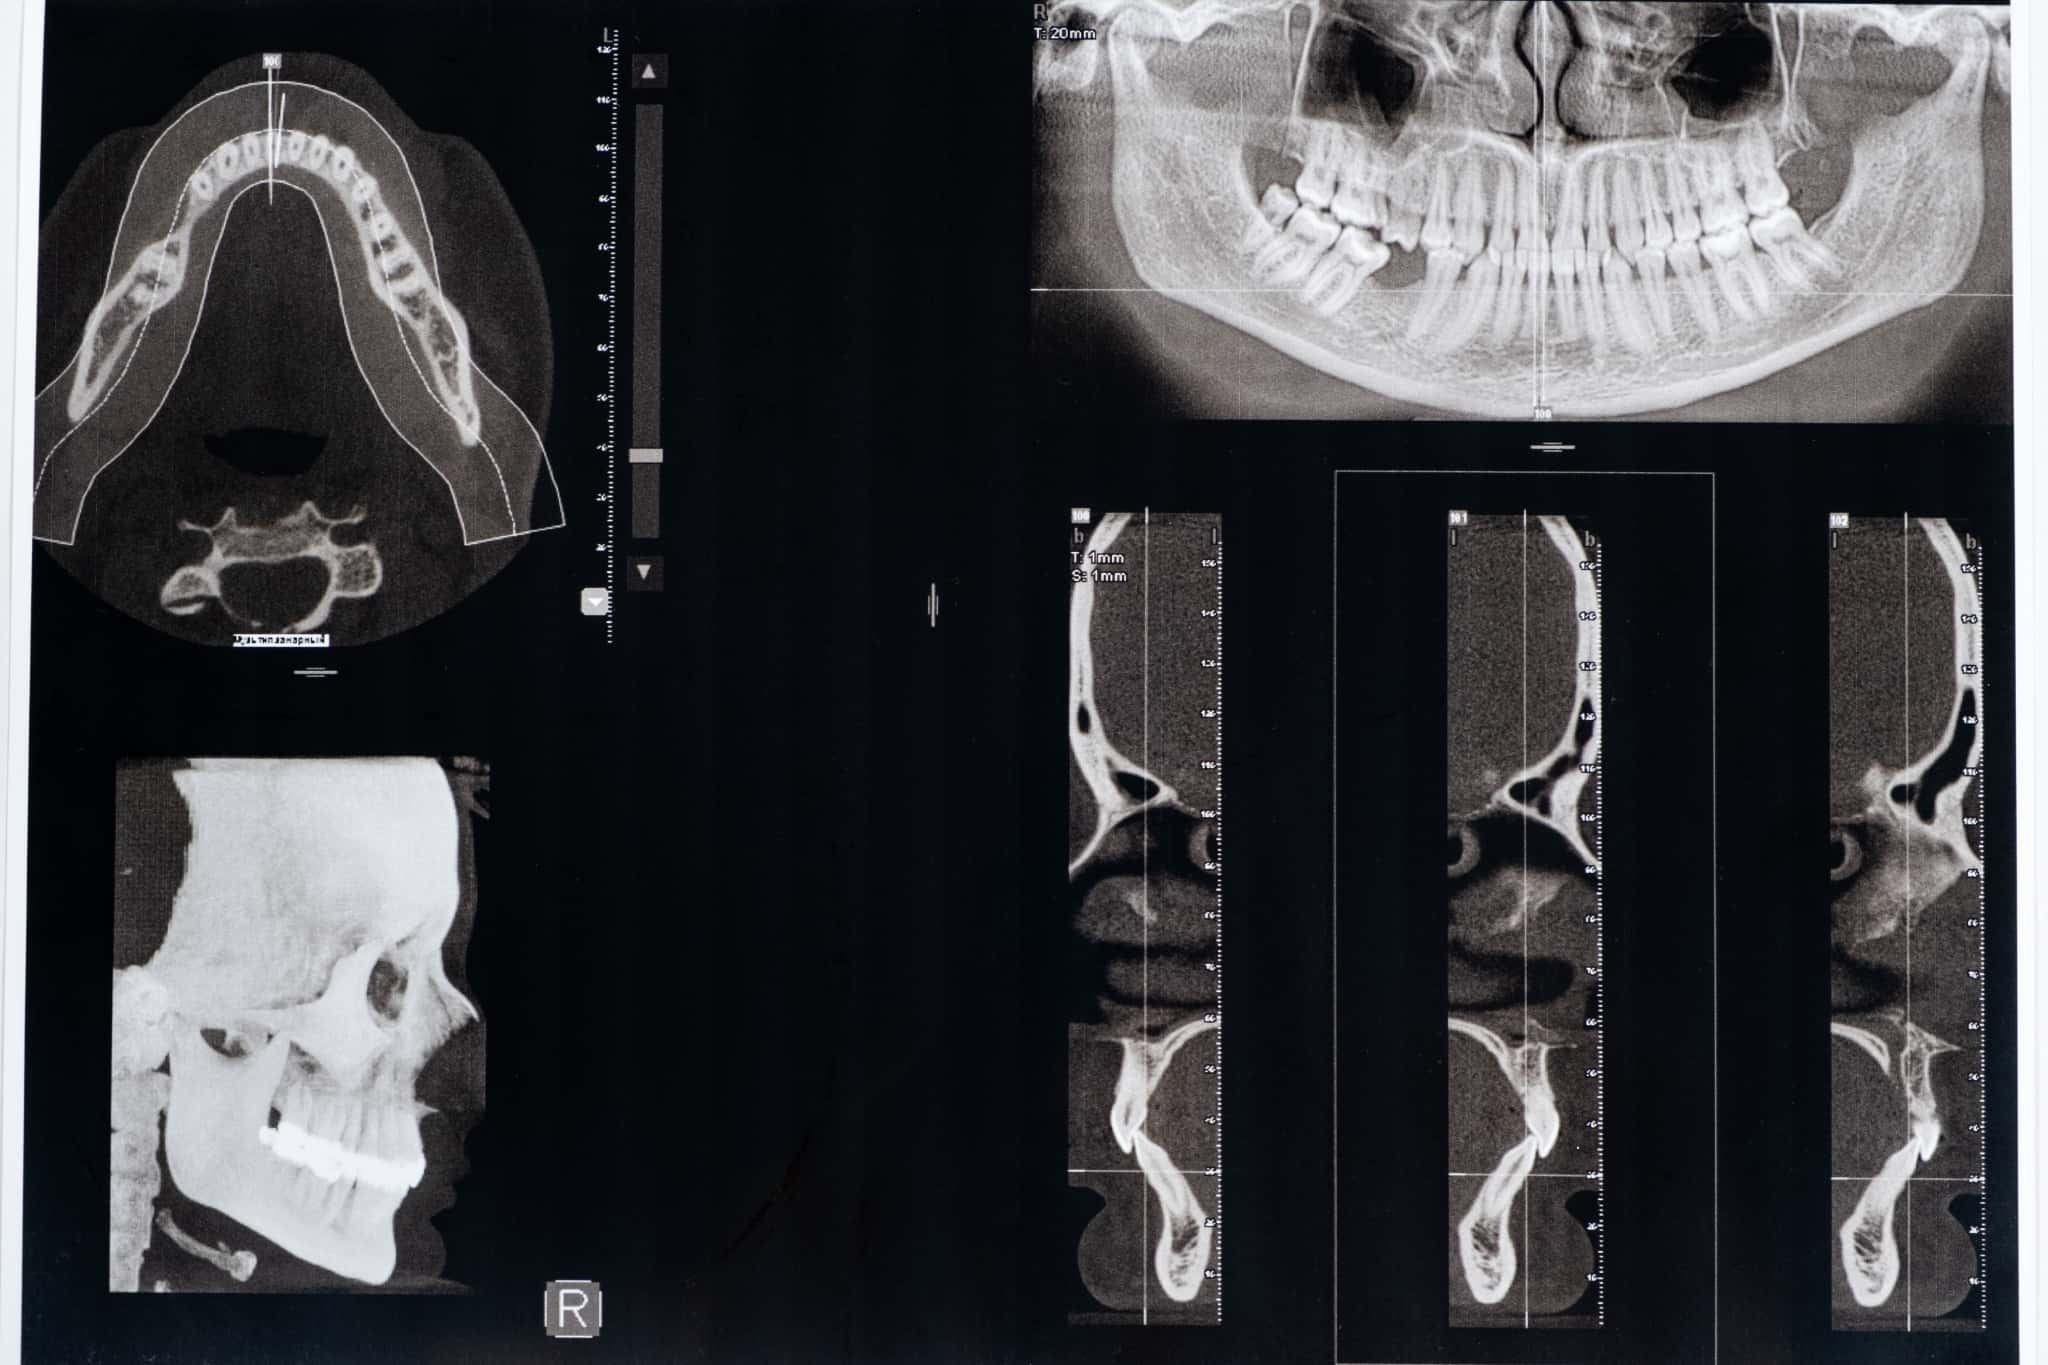

顎関節症の診断は、まず丁寧な問診から始まります。あごの痛みや音の有無、口の開けづらさ、日常生活での支障などについて詳しく確認します。次に、実際にあごの動きや筋肉の状態を手で触れながら診察し、痛みや異常の有無を調べていきます。

さらに必要に応じて、レントゲンやMRIといった画像検査が行われることもあります。こうした検査を通じて、あごの関節や周囲の構造に問題がないかを詳しく確認します。これらの情報をもとに、症状の原因や進行具合を判断し、一人ひとりに合った適切な治療法を検討します。